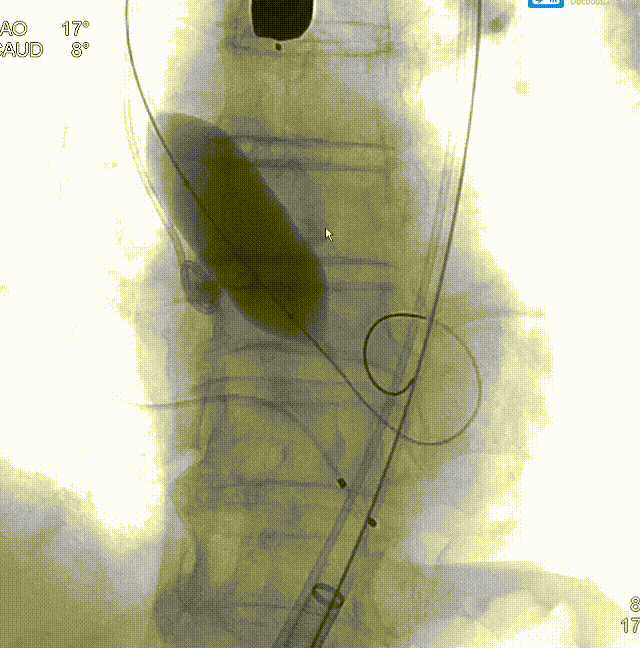

• 跨瓣角度为LAO 17° CAU 8°(右窦中心位)左右,使用22mm球囊预扩张,球囊预扩角度为LAO 17° CAU 8° (右窦中心位)左右;

• 预装AV26瓣膜,释放角度RAO 11° CAU 32°(左右重合)左右,较高位释放(瓣环下0-2mm)。释放后调整至左前斜头位( LAO 35° CRA11°)进一步确定人工瓣膜形态。手术结束后造影评估入路血管情况,避免遗漏血管并发症情况。

主动脉根部造影,少量反流,采用22mm球囊预扩,轻微腰征,造影微量瓣周漏。

球囊预扩

TaurusElite 输送器轻松过弓、跨瓣,TaurusElite AV26精准定位无冠窦最低点。

TaurusElite柔顺过弓

瓣膜定位